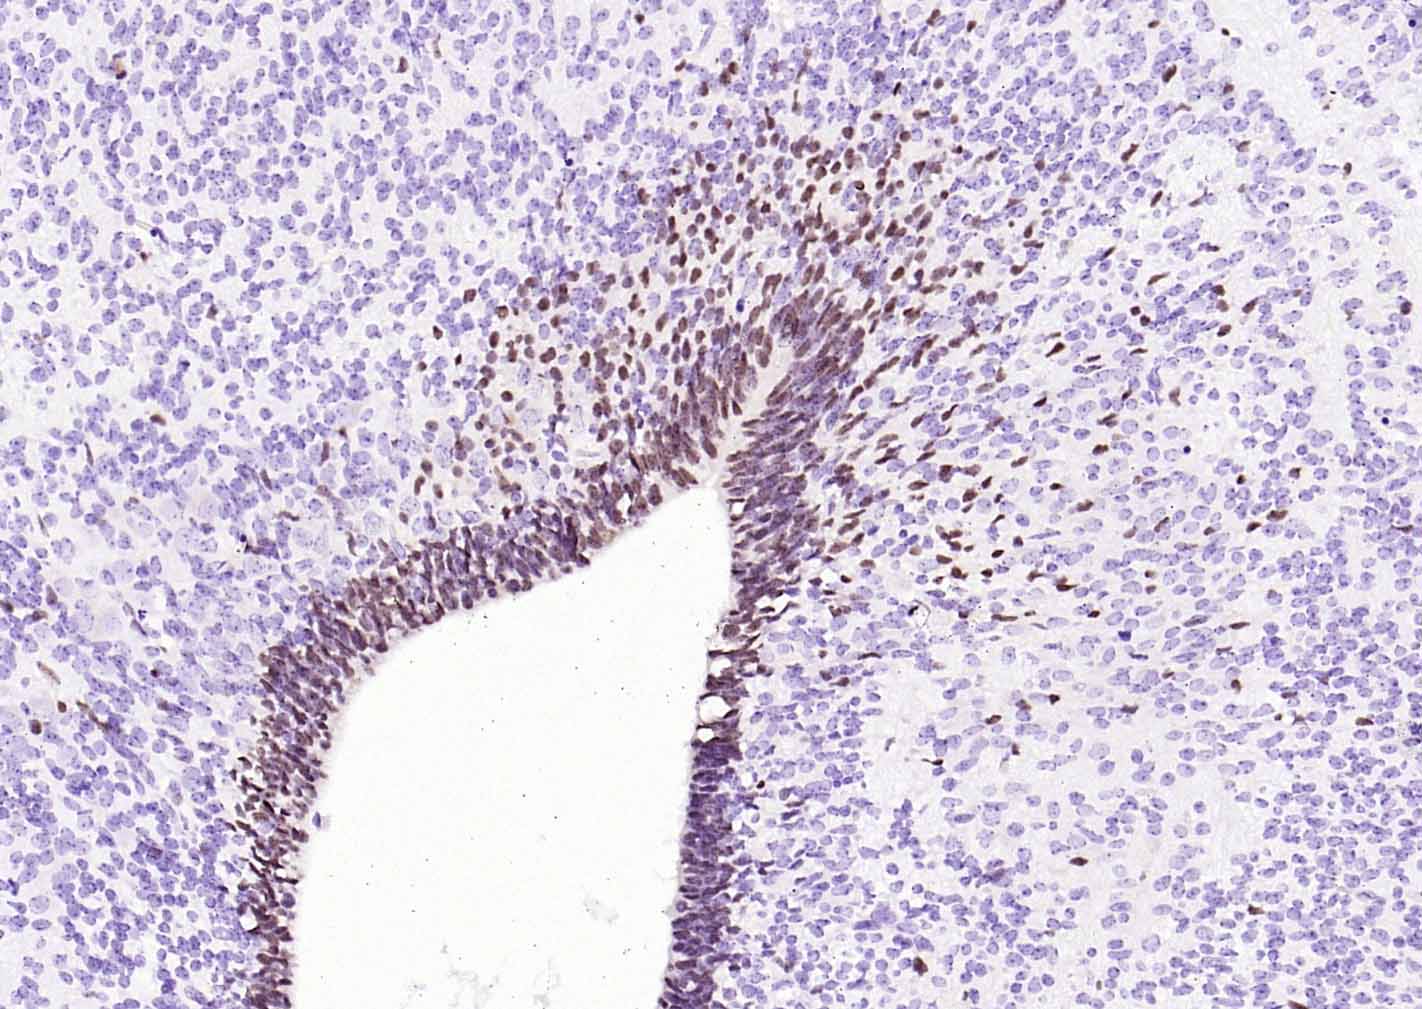

Paraformaldehyde-fixed, paraffin embedded Human Lung Cancer; Antigen retrieval by boiling in sodium citrate buffer (pH6.0) for 15 min; Antibody incubation with SOX2 Monoclonal Antibody, Unconjugated(bsm-60788R) at 1:300 overnight at 4°C, followed by conjugation to the SP Kit (Rabbit, SP-0023) and DAB (C-0010) staining.